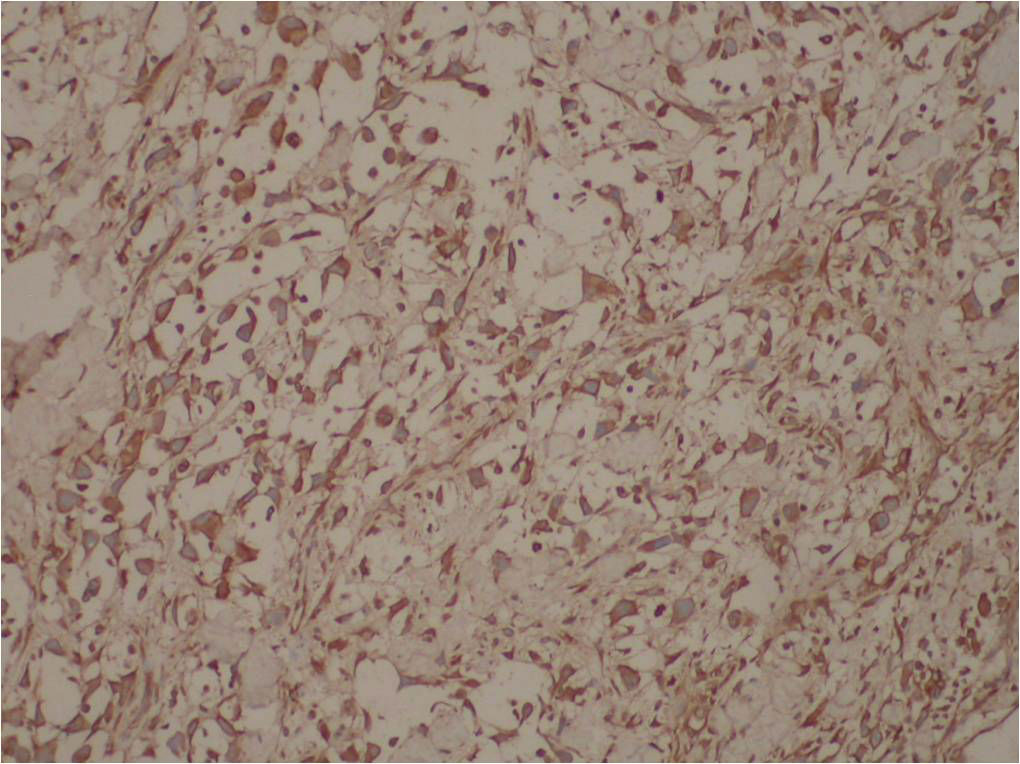

典型的假血管性鳞状细胞癌。

1、肿瘤细胞极度棘层松解而形成假血管腔和囊腔,内含淡蓝色粘液样物及渗出的红细胞。

2、腔壁衬有非典型上皮样细胞,多角形,排列方式小巢状、索条状,核空泡状,核仁明显。被覆皮肤上皮有发育不良现象。

免疫组化结果:

阳性:  CKVimCK5/6CK14

阴性:  MyoD1MyogeninDesminSMAEMACD34HMB45CK8/18CEA

特染:  AB-PAS(-)